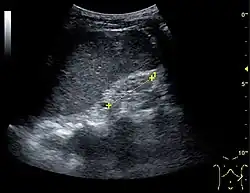

Ultrasound

Kidney ultrasonography is useful for diagnostic and prognostic purposes in chronic kidney disease. Whether the underlying pathologic change is glomerular sclerosis, tubular atrophy, interstitial fibrosis, or inflammation, the result is often increased echogenicity of the cortex. The echogenicity of the kidney should be related to the echogenicity of the liver or the spleen. Moreover, decreased kidney size and cortical thinning are often seen, especially when the disease progresses. However, kidney size correlates to height, and short persons tend to have small kidneys; thus, kidney size as the only parameter is unreliable.[63]